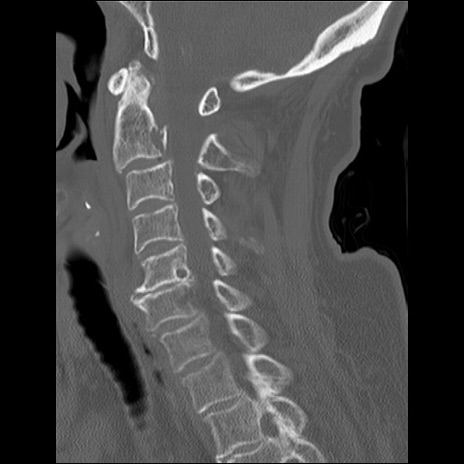

症例48 頚椎CT(矢状断像)

頚椎CT